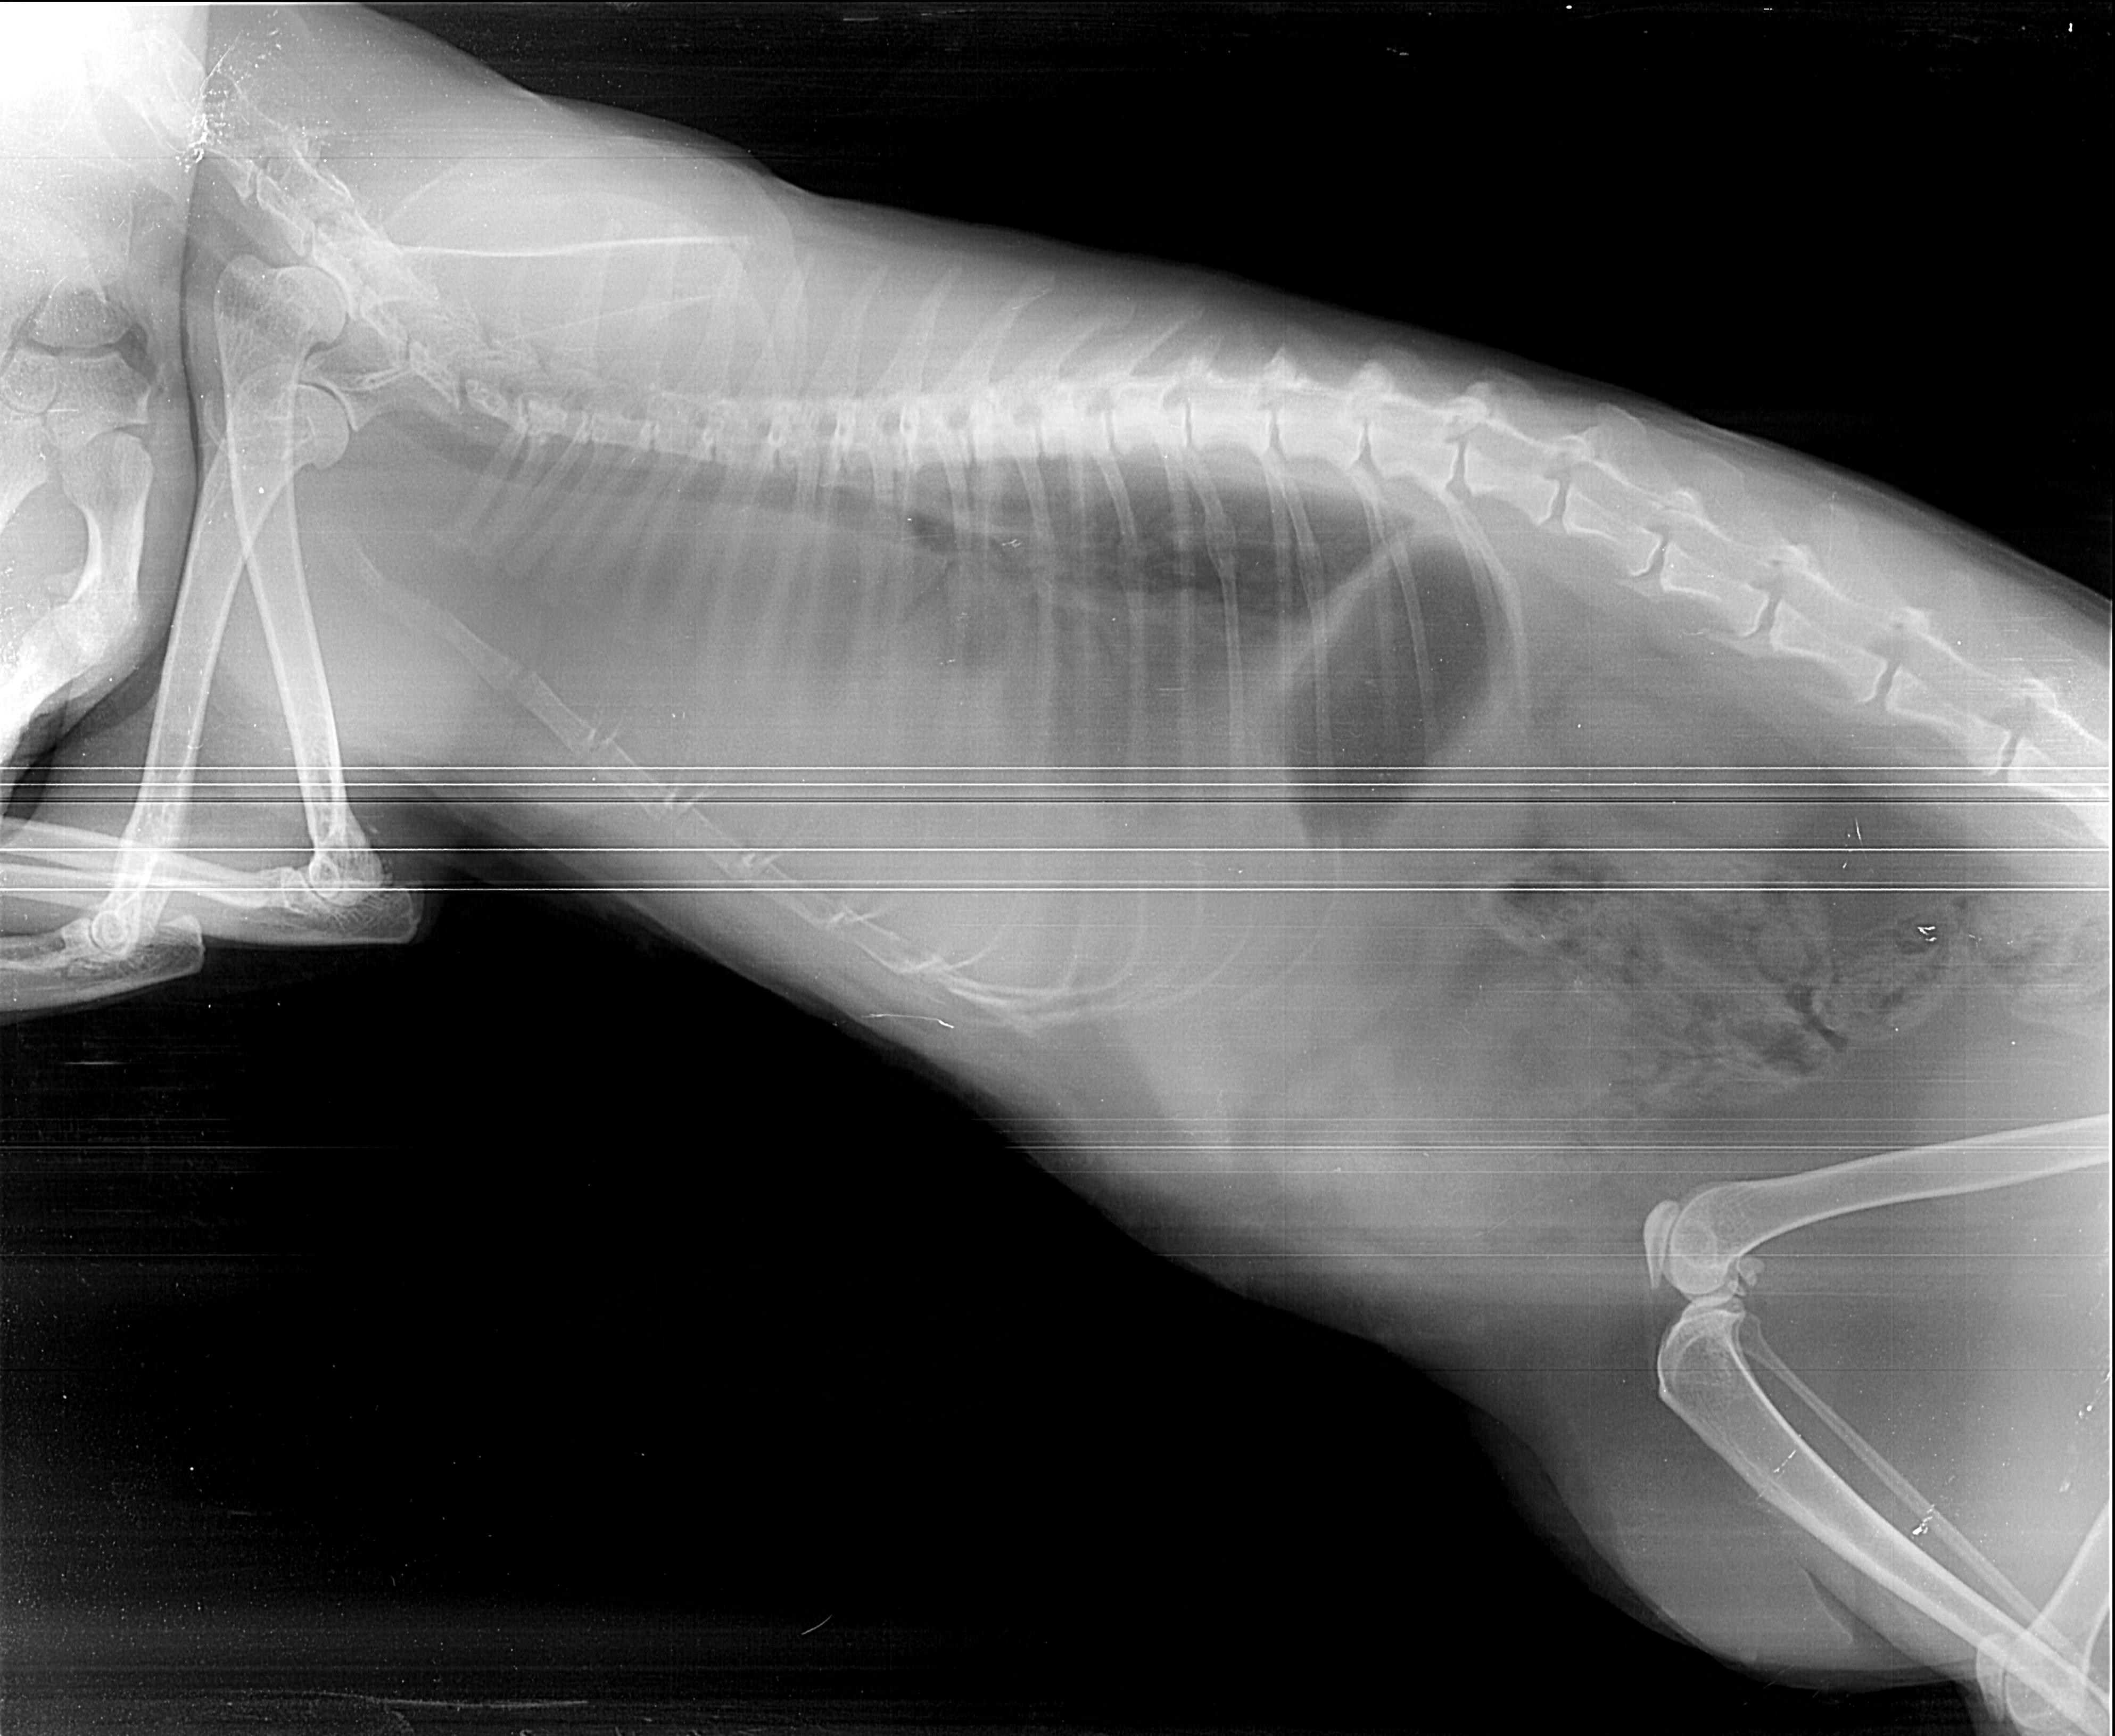

Рентген как метод диагностики легочных гельминтов у кошек: что нужно знать владельцам

Легочные гельминты у кошек – это опасные паразиты, которые могут вызвать серьезные заболевания дыхательной системы. Одним из эффективных методов диагностики является рентгеновское исследование, позволяющее выявить их наличие в легких. В этой статье мы расскажем, как этот метод помогает в диагностике и что нужно знать владельцам домашних питомцев.

Рентген может помочь не только обнаружить гельминтов, но и выявить возможные осложнения в легких.

Для точной диагностики сочетайте рентгеновские снимки с анализами кала на наличие яиц гельминтов.

Рентгеновское исследование помогает выявить даже скрытые инфекции, которые могут не проявляться на начальных стадиях.

После лечения следует повторно пройти рентген, чтобы убедиться в эффективности терапии.